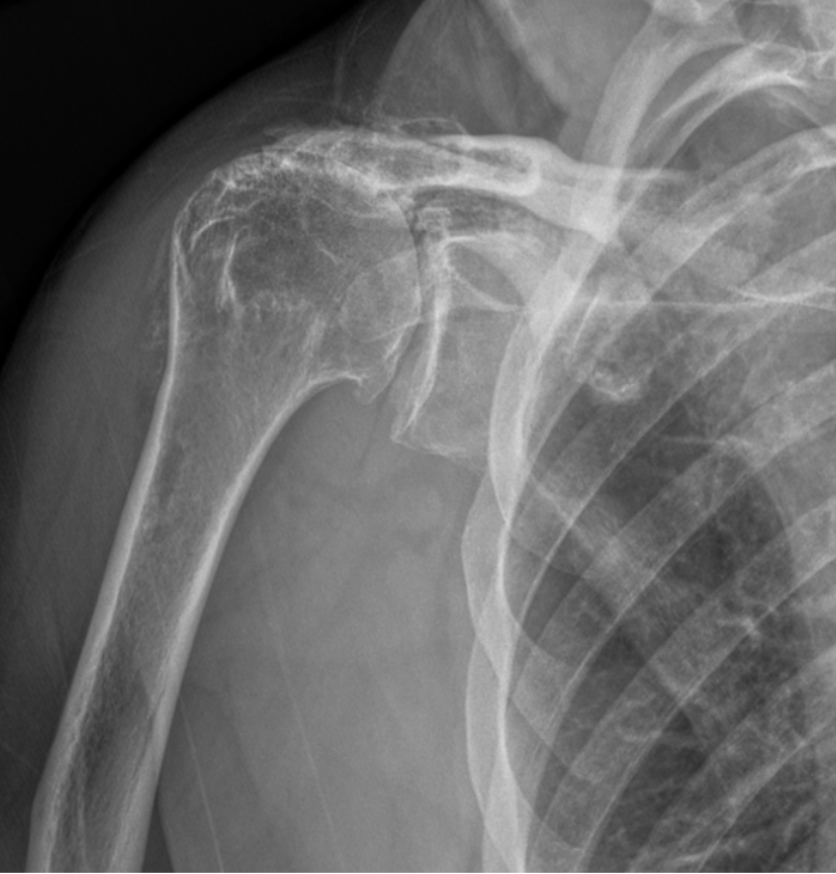

In this specific degenerative condition, the cartilage wears unevenly, often causing the humeral head to shift or tilt within the glenohumeral joint.

This uneven wear leads to asymmetrical joint space narrowing, resulting in pain, stiffness, and limited range of motion.

X-ray image of a human shoulder showing the clavicle, scapula, and upper arm bone (humerus).